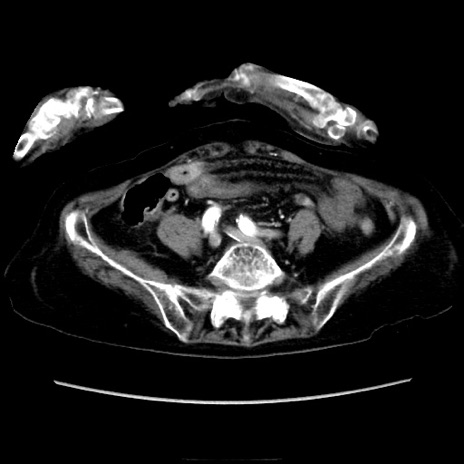

症例40(横断像)

【症例】90歳代女性

【主訴】腹痛・嘔吐

【現病歴】 食欲低下、嘔吐があり昨日他院受診。肺炎と診断され入院となる。入院後より腹部全体に圧痛あり。胃管留置され経過みていたが、症状持続するため、

当院転院となる。

【既往歴】胸椎圧迫骨折、胆石症

【身体所見】腹部:中央に激痛あり、圧痛あり、反跳痛不明

【データ】WBC 17100、CRP 18.82

横断像